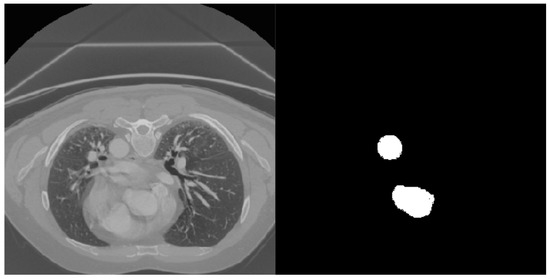

The results obtained are promising but limited by the quality of the annotations. Indeed, the ground truth of the dataset was obtained with a semi-automatic procedure and, in some cases, was not completely accurate. However, the dataset was provided with a reasonable supervision that somehow compensates for the absence of datasets with aortic images labeled at the pixel level. In Figure 5, some images are provided, together with their labels and the segmentation generated by the network, for a qualitative evaluation. Figure 6 shows some slices not correctly segmented by the network. As we can see, in this case, the images are actually difficult to interpret; in the second and third row, in fact, the slices are really dark and, in the first row, the network probably wrongly classified the aorta due to its size.

Figure 5.

Segmentation results on axial (top), coronal (center) and sagittal (bottom) slices. In (d), green represents correctly predicted pixels, blue pixels are present in the label but not predicted as aorta from the network, and red pixels are incorrectly predicted as aorta. (a) Original images; (b) Ground truths; (c) Network predictions; (d) Predictions overlapped with labels and pre-processed original images.